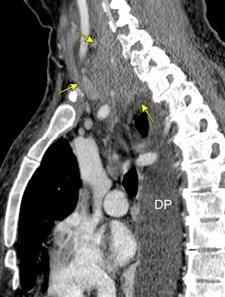

Infección pleural que se disemina a la pared torácica y piel. (Puede drenar espontáneamente)

Organismos: Micobacteria tuberculosa, intracelular. Actinomices

Estreptococo

Estafilococo (raro)

Signo específico: Expansión parietal con la tos

Neumonía por Estrept. neumonía. Derrame pericárdico. Empiema necesitatis (tubo de drenaje)

Edema de los tejidos extrapleurales subcostales (60%, 21 of 35).Takasugi et al. The extrapleural fat in empyema: CT appearance. Br J Radiol 1991